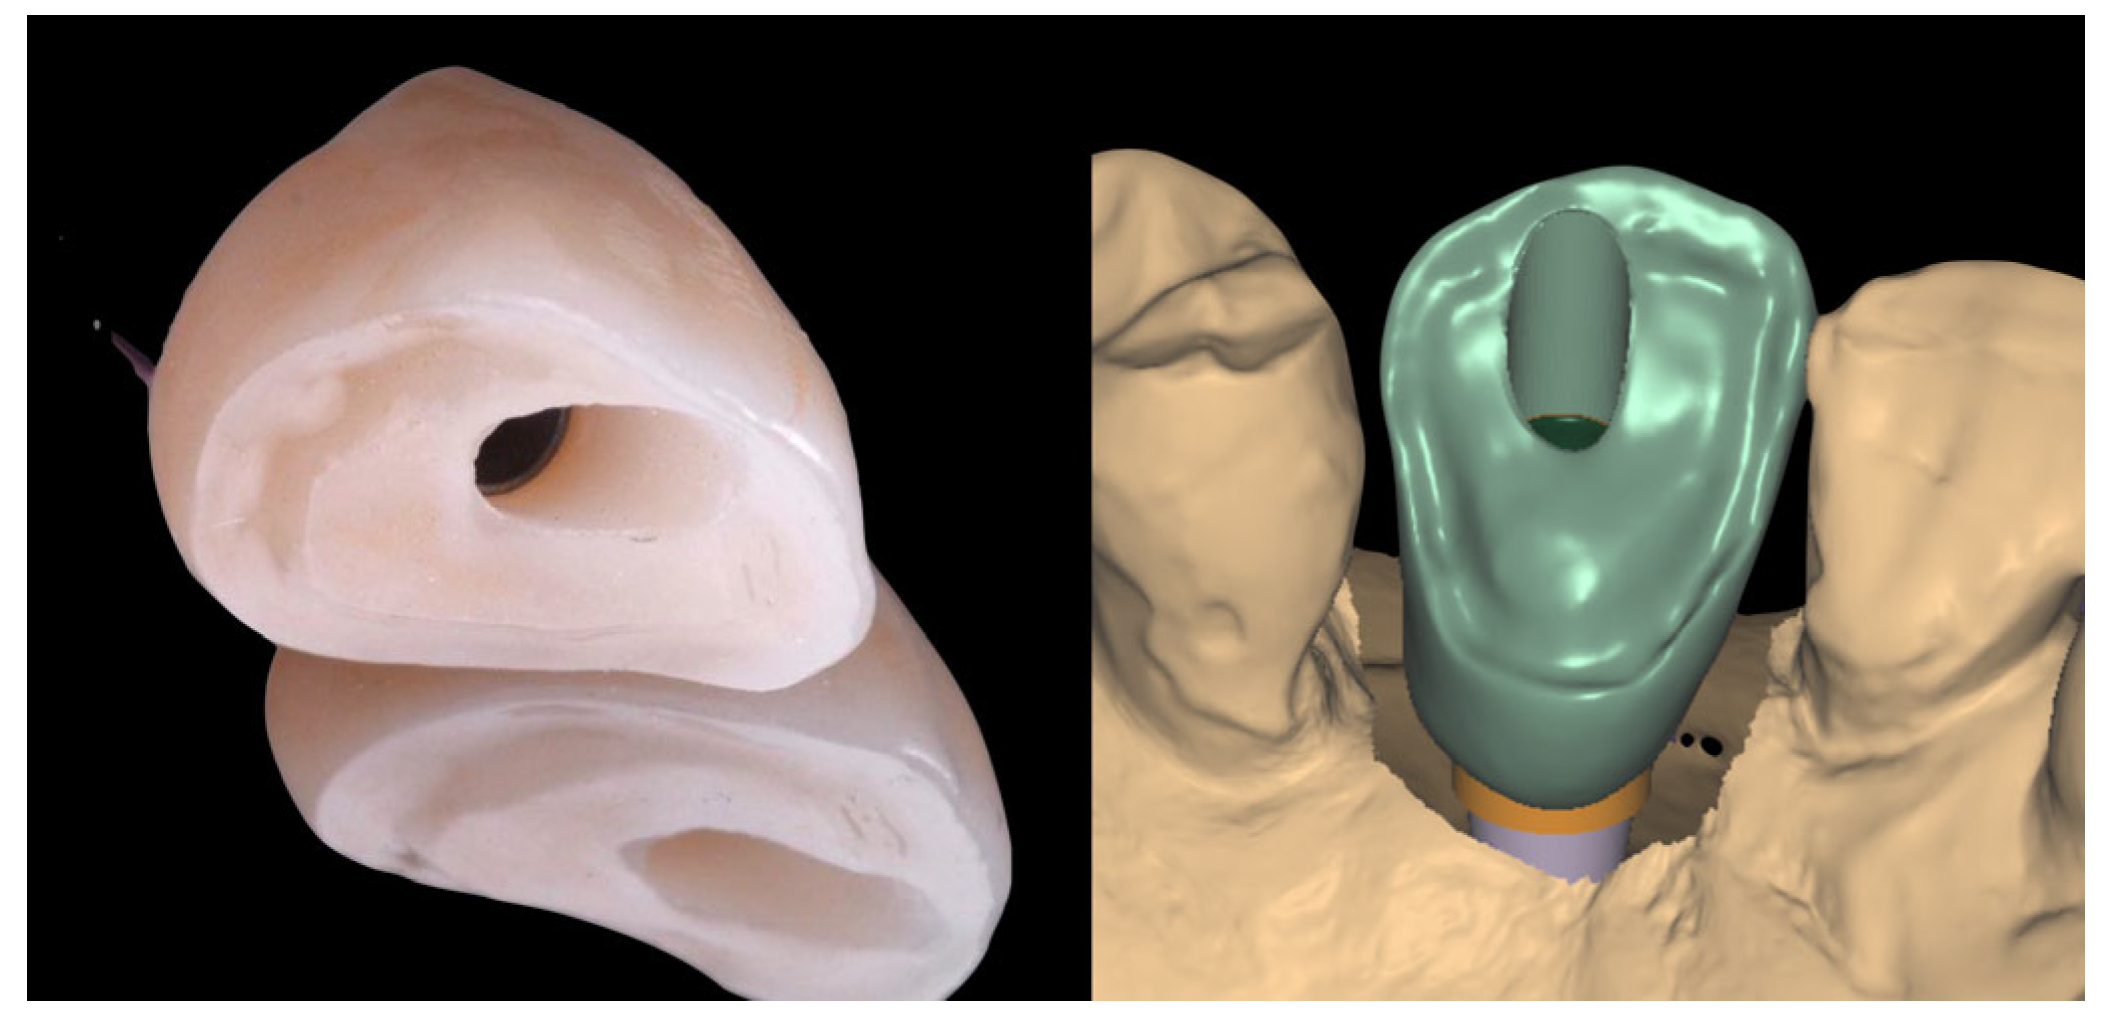

2.3. Laboratory Procedure

2.4. Crown Delivery